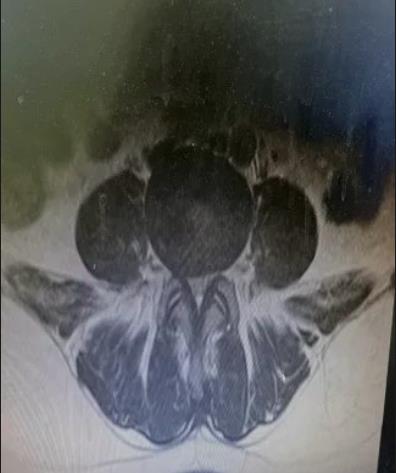

60岁的王某,女性,有3年“腰椎间盘突出伴椎管狭窄”病史。最近,她的腰痛加重,感觉到疼痛向双侧臀部放射,伴有双下肢沉重感。只能走大约300米就需要停下来休息,给她的日常生活带来很大困扰。王某来到市中心医院就诊,与骨科一病区医师详细交流,经仔细检查,发现患者病情比较严重,保守治疗效果不佳,而且狭窄部位比较深,采用普通的单轴椎间孔镜手术可能效果不好。经过骨一科医疗团队共同讨论,决定采用创伤小、恢复快、椎管减压更彻底的微创方案-UBE技术进行治疗。

做好充分准备后,程福宏主任、雷广宇副主任、张波副主任医师和张楠副主任医师等人共同合作,术中采用两个约1cm的切口,通过通道进行操作,对狭窄部位进行减压(ULBD),并摘除了突出的髓核。术后,患者明显感觉到双下肢松弛,可以自如行走,第二天手术后满意出院。